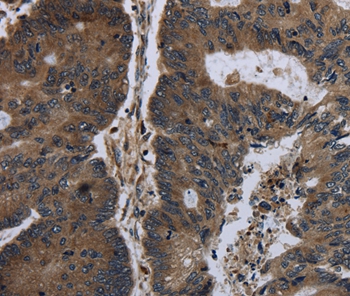

Immunohistochemical analysis of paraffin-embedded Human gastric cancer tissue using #36400 at dilution 1/20.

Immunohistochemical analysis of paraffin-embedded Human colon cancer tissue using #36400 at dilution 1/20.